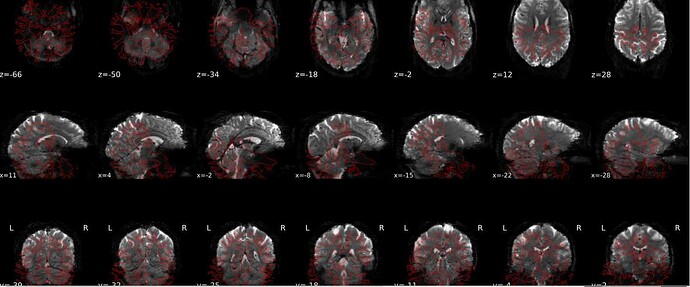

We’ve encountered a problem of misalignment between EPI and T1W. The Freesurfer bbregister failed to align EPI and T1w as well as Freesurfer mri_coreg. While the recon output seems to be alright in the fmriprep output report but it’s in a different orientation when being viewed in fsleyes. Can you kindly provide any suggestions?